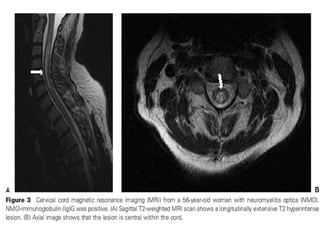

• TM manifesting as a neuromyelitis optica spectrum disorder.

NMOD diagnostic crteria